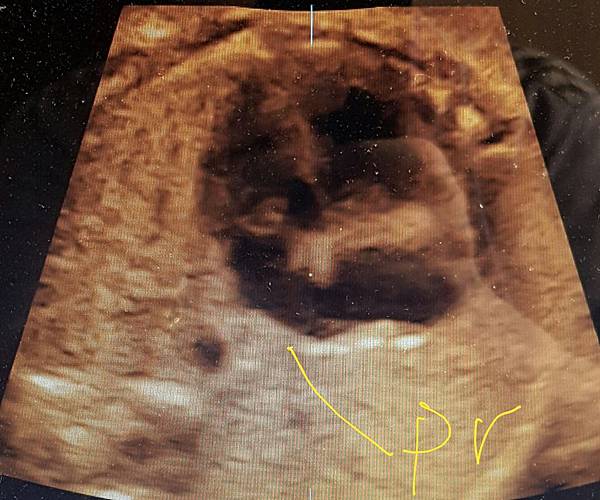

我看肺靜脈的心路歷程可以分成三個階段,第一個階段是用gray scale(黑白)看到左右肺靜脈下行支回到左心房(附圖 1.2.),第二個階段是用flow(彩色)看到左右肺靜脈回到左心房(附圖 3.4.),第三階段是同時要看到黑白和彩色的左右肺靜脈回到左心房,為什麼只有看flow(彩色)不安全呢?因為右肺靜脈的flow有時候是假影,為何會看到假影?因為右心房到左心房的flow overlapping(重疊)造成的(附圖 5.),如何判斷是假影,只要關掉flow看黑白的即可證明右肺靜脈沒有進入左心房(附圖 6.)。

如果同時看到左右肺靜脈進入左心房,這種誤判的機率下降很多,如果只能看到一條肺靜脈的血流,我會選擇左肺靜脈(附圖 7.8.),因為左肺靜脈的血流比較不會被overlapping,最安全的方法是黑白和彩色都看到左右肺靜脈進入左心房,只是需要胎兒姿勢配合,當然孕婦的體重也是需要考量的因素。